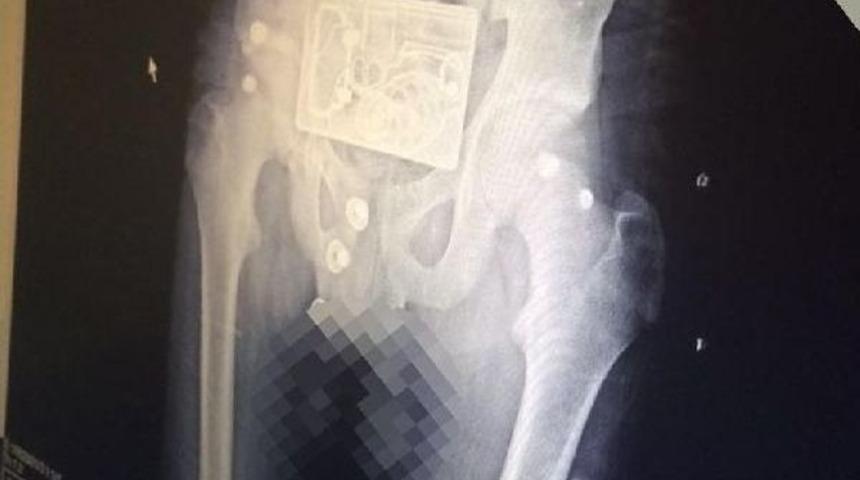

Berktuğ ÖNCÜ/BURSA, Kısa süreli panik ve korkuya neden olan olay, Bursa'da Sağlık Bakanlığı'na bağlı Yüksek İhtisas Hastanesi’nde yaşandı. Bacağındaki rahatsızlık nedeniyle hastaneye gelen Azerbaycan uyruklu M.O. röntgen servisine gönderildi. Burada pantolonu çıkarmadan çekilen röntgen filmine gencin taktığı metal tokanın görüntüsü de yansıdı. Tokadaki tabanca, el bombası ve mermi desenlerini gencin beline bağladığı bomba zanneden görevli durumu polise bildirdi.

Hastanede kısa süreli panik yaşanırken, polislerin incelemesi sonrası gercek ortaya çıkınca genç serbest bırakıldı.